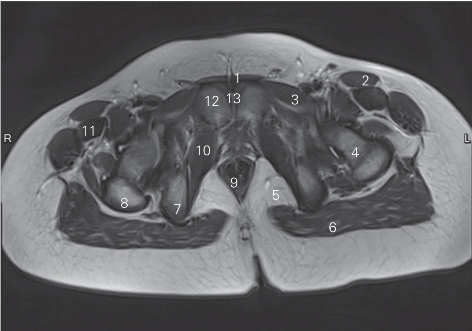

图5-5 经股骨颈横断层的MR T1加权图像

1 腹直肌 rectus abdominis 2 缝匠肌 sartorius

3 耻骨肌 pectineus 4 股骨颈 neck of femur

5 坐骨肛门窝 ischioanal fossa 6 臀大肌 gluteus maximus

7 坐骨结节 ischial tuberosity 8 大转子 greater trochanter

9 肛管 anal canal 10 闭孔内肌 obturator internus

11 股直肌 rectus femoris 12 耻骨上支 superior ramus of pubis

13 耻骨联合 pubic symphysis